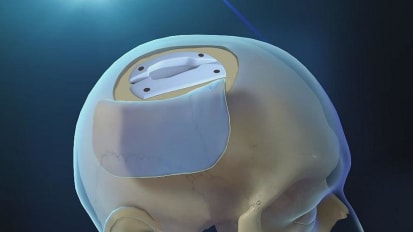

New study by Johns Hopkins Medicine neuroplastic and reconstructive surgeons under Chad Gordon shows “undercover” implant between scalp and skull successfully treats brain swelling known as hydrocephalus.

Patients diagnosed with idiopathic normal pressure hydrocephalus (iNPH), a type of brain swelling most commonly seen in older adults — and for which the underlying cause is unknown — are typically treated by surgically installing a shunt ...